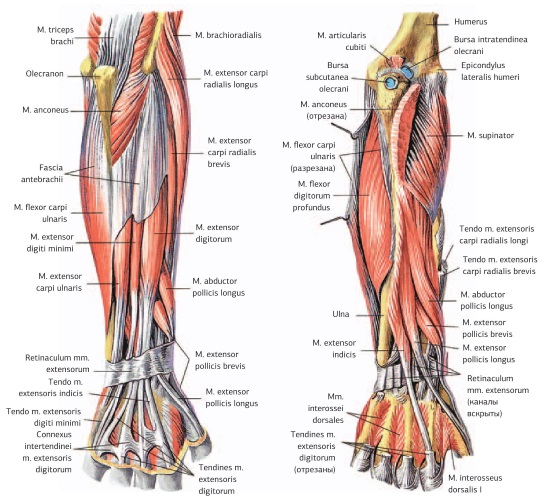

Анатомия и функции мышцы brachioradialis